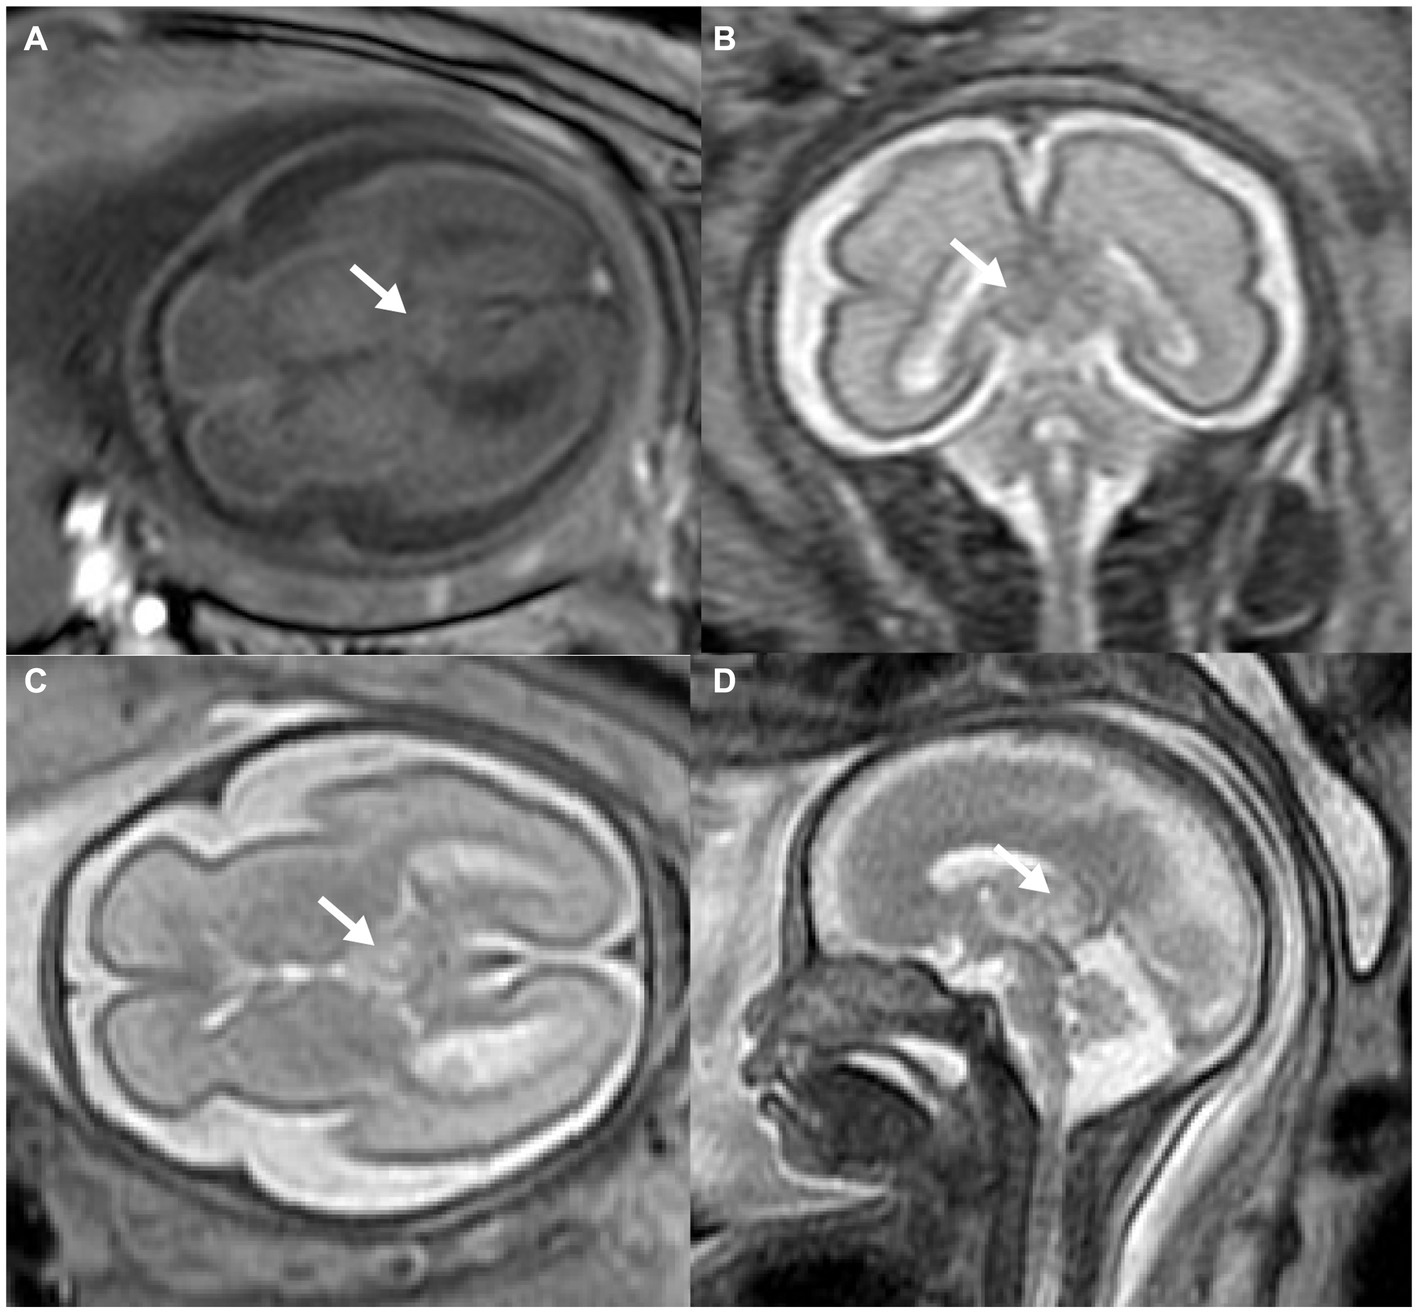

MRI was then used to investigate the fetal brain in a 1.5 Tesla mode at 26 weeks of gestation, which revealed abnormal echogenicity with unclear margins between the bilateral thalamus. The mass was hyperintense on both T1-weighted magnetic resonance imaging (T1WI) and T2-weighted magnetic resonance imaging (T2WI) as compared to the surrounding brain tissue (Figures 2A–D). Amniocentesis was performed for conventional karyotype analysis and chromosome microarray analysis, which demonstrated no anomalies.

Figure 2

Prenatal MRI of fetal intracranial medulloepithelioma. MRI of the fetal brain: axial view of T1WI (A), coronal (B), axial (C), and sagittal (D) view of T2WI; white arrow indicates the tumor.

On magnetic resonance imaging, both masses showed poorly-circumscribed margins. While it displayed hypointense to isointense signals on both T1WI and T2WI compared to the nearby cerebral cortex in the case reported by Nidhi et al., the mass exhibited homogeneous isointense to hyperintense signals on both T1WI and T2WI. These discrepancies may be attributed to the small size and abundant blood flow of the tumor in our case. Additionally, it was also hyperintense on T2WI in other cases diagnosed in childhood (4, 6, 7). Moreover, the tumors in both cases were located outside the brain tissue, clearly separated from the brain parenchyma. Both tumors displayed a papillary, glandular tubular arrangement and formed a pseudostratified epithelium that resembled the structure of the primitive neural tube as well as multilayered rosettes. At the molecular level, embryonic tumors with multilayered rosettes can be categorized into two subtypes based on the status of DICER1 gene mutants and chromosome 19 miRNA cluster (C19MC) amplification (2). In this case, neither C19MC amplification nor the DICER1 mutation was tested, but this did not rule out the diagnosis of medulloepithelioma based on pathological evidence.